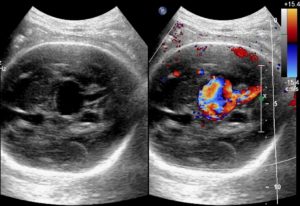

The diagnosis of VOGMs is typically postnatal, but it can be detected antenatally in approximately 29% of cases. On antenatal ultrasound, VOGMs are generally observed from 25 weeks of gestation and may appear as cystic midline brain lesions, as demonstrated in the ultrasound image, Figure 2. Color Doppler imaging can then reveal abnormal blood flow, a finding sometimes referred to as the ‘comet tail’ sign, as shown in Figure 3. Antenatal magnetic resonance imaging (MRI) can also be used to confirm the diagnosis. It allows evaluation of any brain injury and helps with planning delivery in a facility with the necessary resources and expertise [7].

Figure 3. Antenatal ultrasound demonstrating the ‘comet tail’ sign [9].